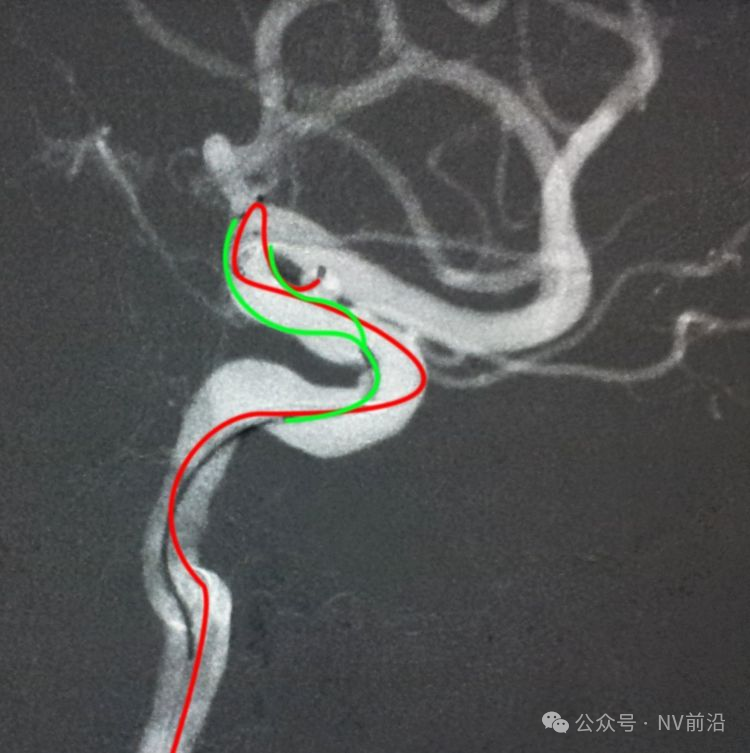

Echelon 10微导管头无论塑成C形还是S形,均无法稳定于动脉瘤腔内,遂使用回马枪技术,使微导管成襻通过,管头折返入瘤腔。

跨瘤颈释放Solitaire 4×20支架(蓝线),压住微导管(红线),在支架保护下经返折的微导管送入弹簧圈填塞瘤腔。